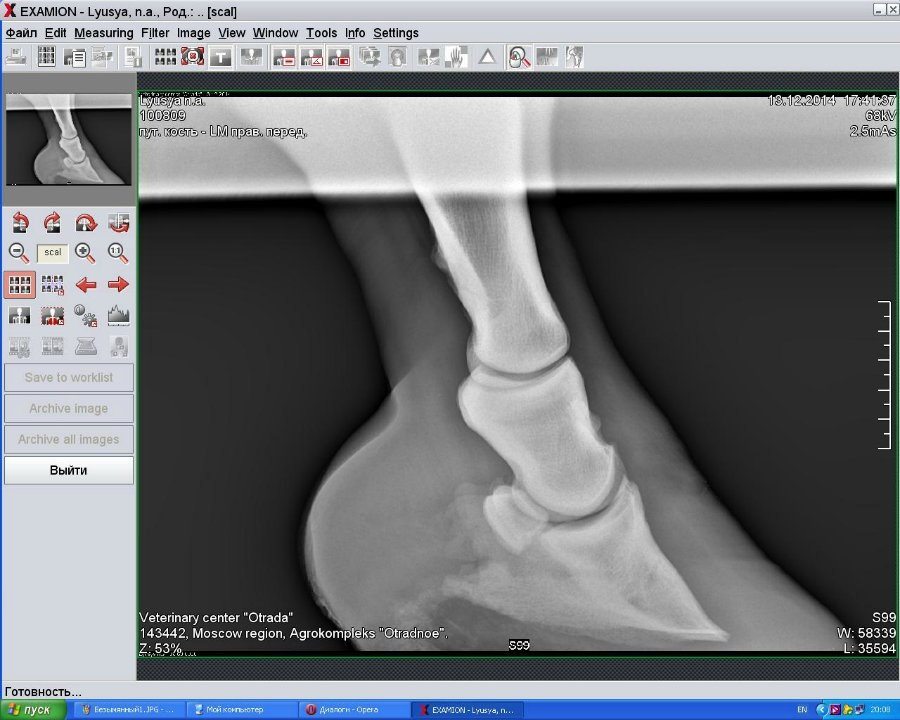

Правый перед(2014)